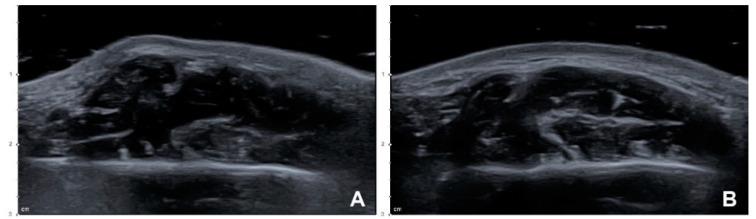

The aim of the study was to propose a more efficient and safer botulinum toxin type A (BoNT-A) injection method for the masseter by comparing the conventional blind injection and a novel ultrasonography (US)-guided injection technique in a clinical trial. The 40 masseters from 20 healthy young Korean volunteers (10 males and 10 females with a mean age of 25.6 years) were included in this prospective clinical trial. The BoNT-A (24 U) was injected into the masseter of each volunteer using the conventional blind and US-guided injection techniques on the left and right sides, respectively, and analyzed by US and three-dimensional (3D) facial scanning. One case of PMB (paradoxical masseteric bulging) was observed on the side where a conventional blind injection was performed, which disappeared after the compensational injection. The reduction in the thickness of the masseter in the resting state differed significantly at 1 month after the injection between the conventional blind injection group and the US-guided injection group by 12.38 ± 7.59% and 17.98 ± 9.65%, respectively ((19) = 3.059, = 0.007). The reduction in the facial contour also differed significantly at 1 month after the injection between the conventional blind injection group and the US-guided injection group by 1.95 ± 0.74 mm and 2.22 ± 0.84 mm, respectively ((19) = 2.908, = 0.009). The results of the study showed that the US-guided injection method that considers the deep inferior tendon by visualizing the masseter can prevent the PMB that can occur during a blind injection, and is also more effective.

本研究旨在通过临床试验比较传统盲注法和新型超声(US)引导注射法,提出一种更有效、更安全的咬肌肉毒毒素 A(BoNT-A)注射方法。该前瞻性临床试验纳入了 20 名健康年轻韩国志愿者(10 名男性和 10 名女性,平均年龄 25.6 岁)的 40 侧咬肌。志愿者两侧咬肌分别采用传统盲注法和 US 引导注射法,各注射 24U BoNT-A,采用 US 和三维(3D)面部扫描进行分析。1 例采用传统盲注法的志愿者出现了 PMB(反常性咬肌膨隆),补偿性注射后消失。注射后 1 个月,传统盲注组和 US 引导注射组在休息状态下咬肌厚度的减少分别为 12.38%±7.59%和 17.98%±9.65%,差异有统计学意义(t=-3.059,P=0.007)。注射后 1 个月,传统盲注组和 US 引导注射组在面部轮廓的减少分别为 1.95±0.74mm 和 2.22±0.84mm,差异有统计学意义(t=-2.908,P=0.009)。研究结果表明,通过可视化咬肌考虑深层下颌腱的 US 引导注射方法可以预防盲注时可能发生的 PMB,并且更有效。